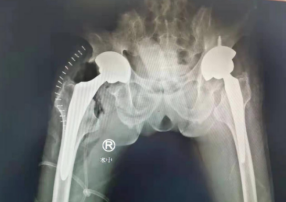

因为吕师傅身患两种“不死的癌症”,病情拖延时间久,比较复杂,张贯林副院长和蒋守海主任张玉帅陈强团队一起,进行了严谨周全的术前评估和分析,制订了万无一失的手术计划与步骤,在间隔一周的时间内,张院长和蒋主任手术团队为患者先后进行了两侧全髋关节置换手术。术中,手术团队以改良Gibson入路,切开阔筋膜,显露髋关节囊,切开,骨刀去除增生骨赘,脱出股骨头,摆锯截骨,取出坏死的股骨头,清理,依次安装髋臼假体、股骨柄、股骨头,测试髋关节活动稳定无脱位,透视全髋关节假体位置合适。手术很顺利、成功。

术后